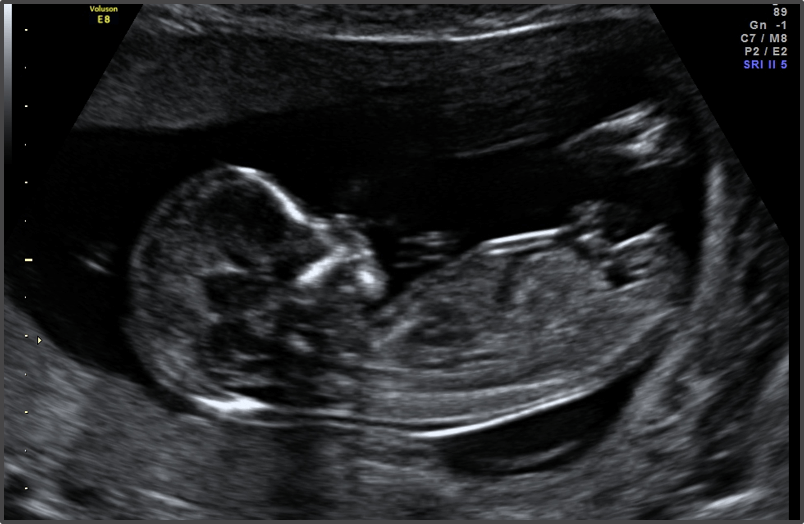

Your baby is now officially in the second trimester.

Baby is the size of Lemon

Approx Baby Weight: 23g

Approx Baby Size: 7.4 cm